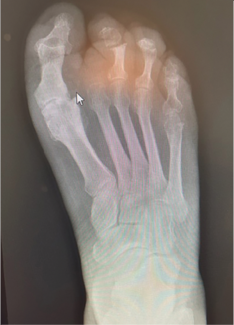

Given that more than half of diabetic foot ulcers can become infected, prompt and accurate diagnosis can be life- and limb-saving. These authors provide an overview of diagnosis and specimen collection for soft tissue infection and...